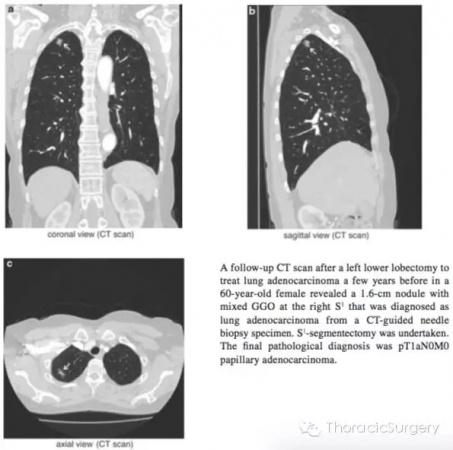

患者,女性,60岁,几年前曾行左下肺叶切除术,CT随访发现S1段1.6cm的混合性GGO结节,CT-引导下穿刺活检病理证实为肺腺癌。 该患者被予以S1-段切除。最后病理诊断为pT1aN0M0**状腺癌。

图.3.1.1通过HRCT影像从轴向,冠状面和矢状面明确肺段动脉,静脉和支气管。气管插管后通过支气管镜进一步明确B1,B2和B3分支形状和尺寸。本书中的图片是段支气管静脉和动脉最常见的分支类型,即右上支气管分为B1和B2和B3;A1和A3段间动脉分支源于肺动脉上干。A2a是源于肺动脉上干的反支,A2b为A2的升支;段间静脉源于尖段和中央静脉。第三肋间推荐作为S1-段切除的主操作孔。